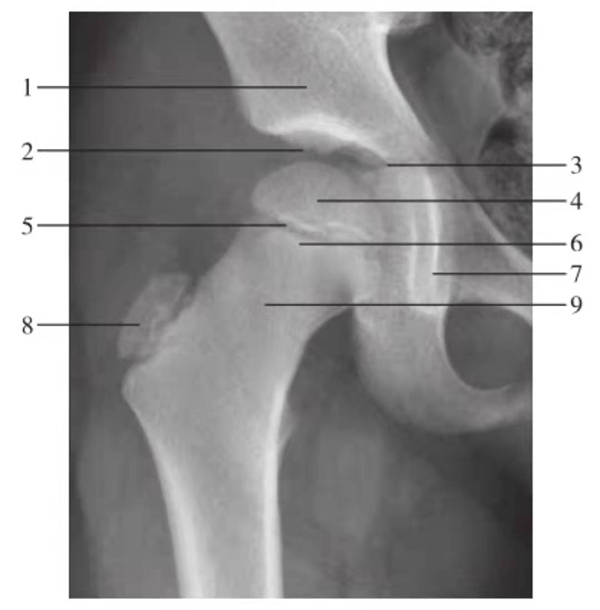

图1 髋关节正位片(生长期,9岁)

1.髂骨;2.髋关节间隙;3.Y形软骨;4.股骨头骨骺;5.骨骺板;6.临时钙化带;7.泪滴;8.大转子骨骺;9.股骨颈